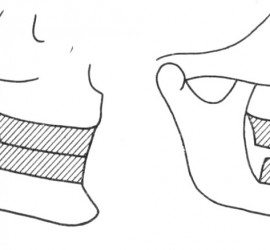

Опорными частями являются кламмеры или замковые соединения, телом — седловидный базис с искусственными зубами. Жевательное давление, падающее на тело съемного мостовидного протеза, передается так же, как и в несъемном, на опорные зубы. Ткани, лежащие под телом протеза, не испытывают непосредственно жевательного давления. Большим преимуществом съемных мостовидных протезов является то, что одним протезом можно соединить различные группы зубов, например, жевательные с обеих сторон или фронтальные и жевательные. Соединение зубов правой и левой сторон челюсти или зубов, различно функционально ориентированных в одну систему, позволяет укрепить зубы с пораженным пародонтом. Кроме того, расширяются возможности применения мостовидных протезов.